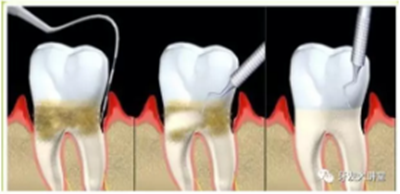

在治療方案上,首先,全口超聲洗牙(齦上潔治)仍然是基礎(chǔ)治療,但遠遠不夠,更專業(yè)的齦下刮治,深牙周袋的處理和微創(chuàng)手術(shù)比如牙齦翻瓣術(shù),松牙固定術(shù)(臨時或永久固定)等等手術(shù)方式與手術(shù)時機的選擇,牙周炎不同分期的不同處理,因為涉及過于專業(yè),除了牙周??漆t(yī)師以外的其他牙醫(yī)甚至很多都從未涉足此領(lǐng)城,在此不再詳述。